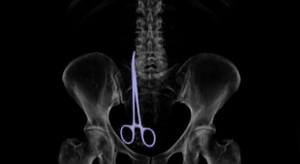

Bà Vera Petrova 63 tuổi (người Nga) liên tục phải chịu đau đớn sau ca phẫu thuật do chiếc kéo dài 16 cm nằm trong ổ bụng.